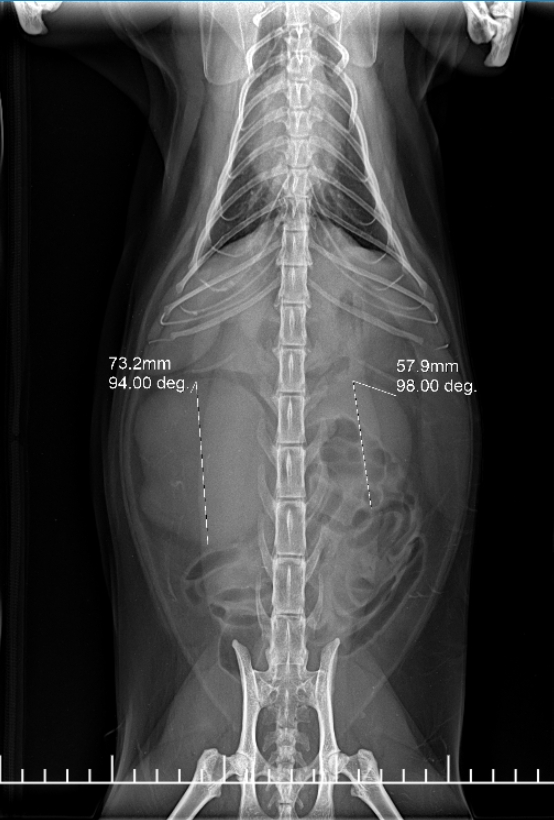

初步理學檢查時,腹部觸診就發現右側有異常腫大結構。透過腹部超音波檢查,我們看到牠的右腎體積明顯放大、形狀不規則,左腎則尚屬正常。這樣的單側腎腫大,最常見的鑑別診斷有:腎臟淋巴瘤、腎盂腎炎或嚴重慢性腎病變。為了釐清原因,我們進行了超音波導引下的細針抽吸,並送檢細胞學檢查。

報告結果顯示:高度懷疑為淋巴瘤。

報告結果顯示: 高度懷疑為惡性淋巴瘤,腎型

到了 化療第4週,我們非常開心地看到:

腫大的右腎已恢復至正常大小!